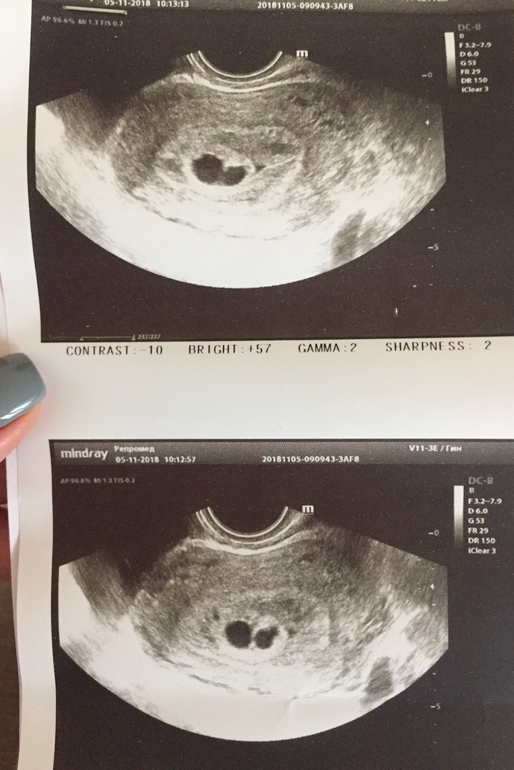

ПЯ с перегородкой. Кто-то встречался с таким явлением?

Срок по М 7,5 недель, по УЗИ 5-6 недель.

Протокол УЗИ прилагаю:

Похоже на двойню ! Здорово! Вы переживали ! Пусть все завершится хорошо.

Вообще похоже на двойню, но ЖТ одно при этом... разве что близнецы, но близнецы в одном плодном яйце вроде как. Вот загуглила, двойня, такое же узи, как у Вас)))

Да, я тоже все пересмотрела) Похоже, но врач не до конца уверенна, и ХГЧ плохо растет. Потому сомнения

Спасибо большое! Я уже ничего не понимаю. Сначала подозревали внематочную, потом неразвивающуюся, теперь вот такой сюрприз на УЗИ. Пугает, что для двойни хгч 16985 низкий. Остается ждать)